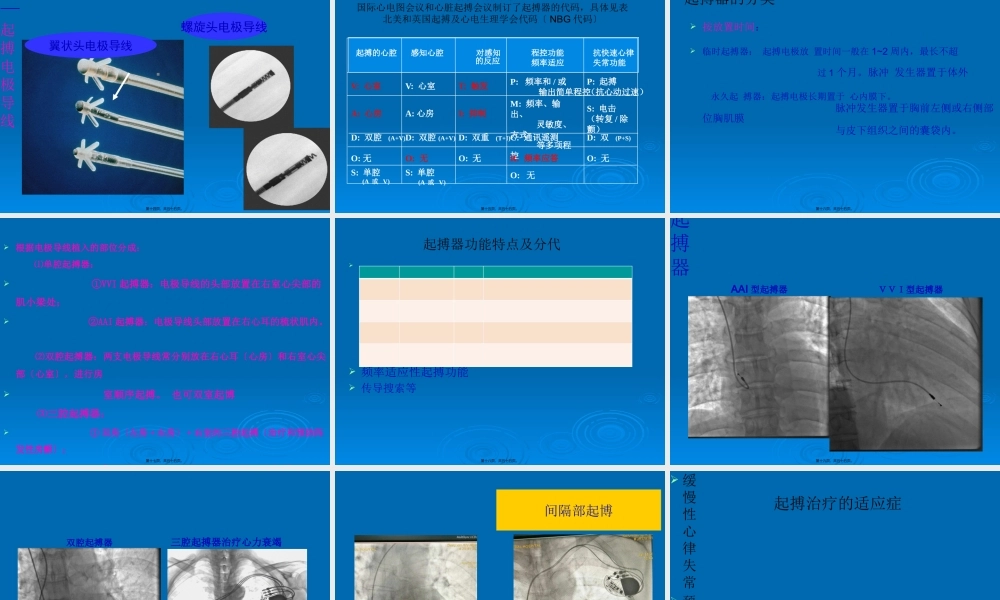

心脏起搏器根底知识宝鸡市中心医院心内科闫业军第一页,共五十五页。起搏器根本概念第二页,共五十五页。生物电传导窦房结发出冲动通过结间束冲动左、右心房——房室结——希氏束——左、右束支——浦肯野纤维——左、右心室窦房结房室结第三页,共五十五页。生理根底——心肌对任何形式的电流刺激都可以产生收缩反响功能:它通过发出的一定形式的微弱脉冲电流,刺激心脏的起搏功能或诱导功能有障碍但的心脏起搏,即以代替正常的起搏点刺激心肌,使之有效地收缩,实现生物机能控制。第四页,共五十五页。作用实际上是提供人造的异位兴奋灶,以代替正常的起搏点来冲动心脏。其对于心肌的兴奋性和收缩功能丧失所致的心脏停搏那么不起作用。第五页,共五十五页。能及原理1.刺激心脏使它除极---最根本的功能2.感知心脏自身电活动---目前也是最根本3.针对窦房结变时功能不全,提供频率适应性起搏〔带R的起搏器才有此功能如:DDDR)4.提供由起搏器存储起来的心电诊断信息(小Holter,不同型号的起搏器此功能不尽相同)第六页,共五十五页。日常活动频率适应性起搏固定频率起搏正常心率150100500睡眠醒来静座走路奔跑休息心率(bpm)心率随活动量改变第七页,共五十五页。的历史1958年全球第一例永久植入型心脏起搏器植入手术在瑞典完成第一台植入人体的起搏器第八页,共五十五页。国瑞典爱立信、宜家家居、沃尔沃汽车伊莱克斯…第九页,共五十五页。起搏器的患者1958年10月8日,IIIAVBkarolinskaStockholm,Sweden,VOO1974年1月22日VVI1989年1月20日VVIR1996年11月7日最后一个VVIR总计更换20台起搏器2001年12月28日卒于与起搏器无关的恶性肿瘤ArneLarsson(1915-2001)第十页,共五十五页。起搏器的历史第一部导线经由静脉植入的人工心脏起搏器(1958年)起搏器的进步第十一页,共五十五页。一—脉冲发生器装有电池,为给心脏发送电脉冲提供能源装有控制起搏器工作的电路第十二页,共五十五页。发生器大小:如男式手表重量:20-80克外壳:钛金属电池:锂-碘电池接口:顶端有电极插孔寿命:6-10年不等第十三页,共五十五页。二—起搏电极导线Screw-InTip翼状头电极导线螺旋头电极导线第十四页,共五十五页。起搏器功能及类型国际心电图会议和心脏起搏会议制订了起搏器的代码,具体见表北美和英国起搏及心电生理学会代码〔NBG代码〕I起搏的心腔II感知心腔III对感知的反应IV程控功能频率适应V抗快速心律失常功能V:心室V:心室T:触发P:频率...

0下载

二年级数学下册期末质检卷(苏教版)二年级数学下册期末质检卷(苏教版)#期末复习 #期末测试卷 #二年级数学 #二年级数学下册#关注我持续更新小学知识.pdf